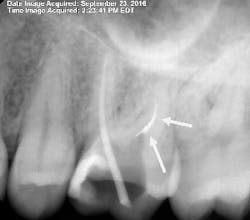

By 2:22 p.m., I was taking periapical x-rays with the gutta-percha to check my working lengths and evaluate the separated files. The x-ray showed that my access wasn’t as open as I originally thought it to be. The canal curved in two places, which caused the file separations. At this point I had two separated files—the 0.1 Twisted File (TF) file and the 15 mm hand file I had used to bypass the canal.

After obturation, it became apparent why the apex locator had given no reading for the DB canal. The foramen was located 3–4 mm away from the apex and on a curve that no file could reach. As a result of copious irrigation, the sealer was expressed from the apex.